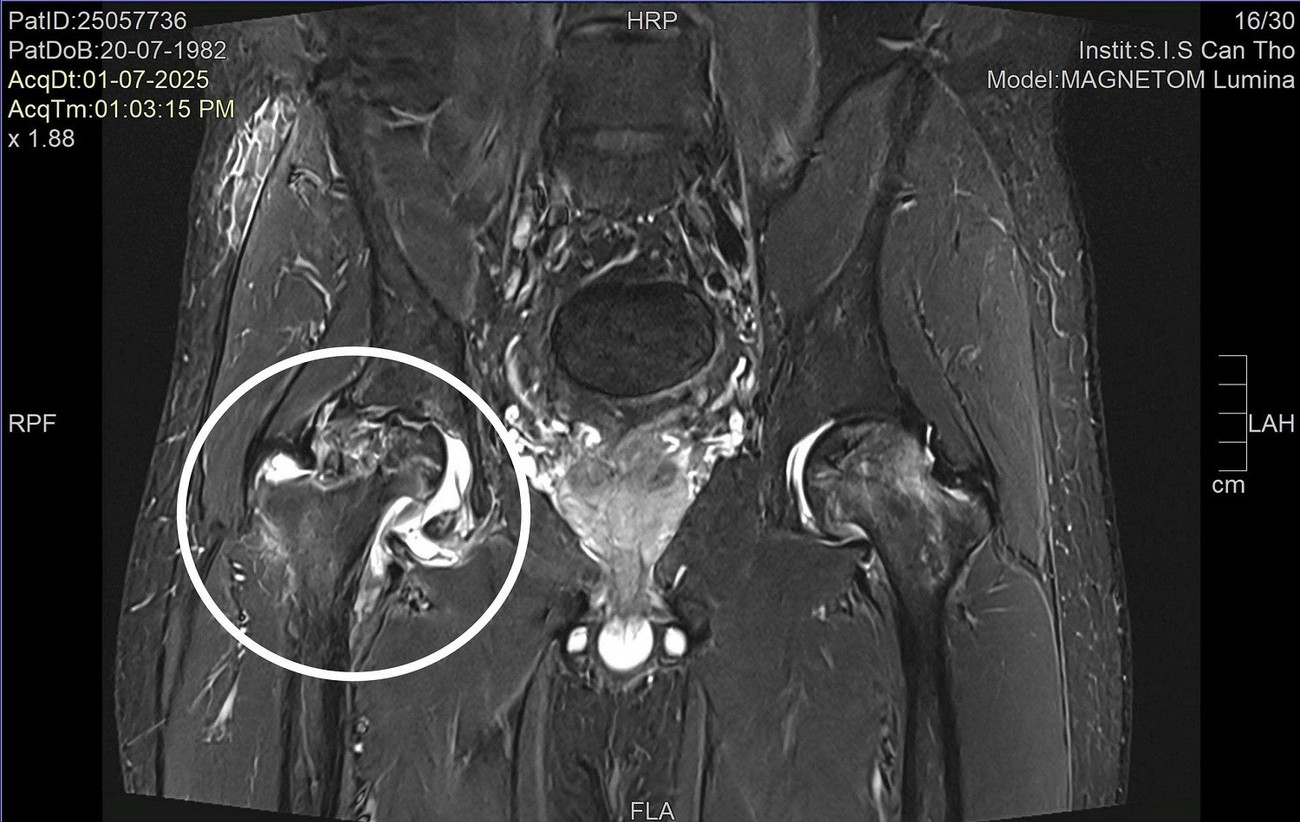

BS Nguyễn Trần Duy, khoa Ngoại Tổng hợp của bệnh viện cho biết, kết quả thăm khám và chụp chiếu tại bệnh viện cho thấy anh V. bị hoại tử chỏm xương đùi cả hai bên với mức độ hoại tử bên phải là độ 3 và bên trái là độ 2. Đây mới là nguyên nhân thực sự gây đau nhức vùng hông và hạn chế sự vận động của người bệnh.

Hoại tử chỏm xương đùi là nguyên nhân khiến người bệnh thường xuyên đau đớn